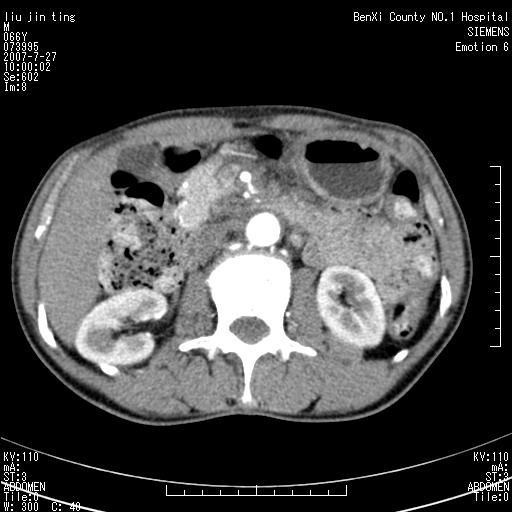

腹痛,背痛,无恶心呕吐,不黄,彩超示胰腺钩癌,ct扫描病灶平扫30-40hu,增强后动脉期40--60hu,静脉期50-68hu,真的是钩突上的么?您要试一试么?

沿着肠系膜上动脉呈匍匐性生长的软组织肿块,形态不规则,包绕肠系膜上动脉,呈明显强化,考虑来源于肠系膜的恶性肿瘤

肠系膜根部肿块,累及肠系膜上动脉,考虑肿大淋巴结累及肠系膜上动脉.

腹腔干至肠系膜上动脉水平肿大淋巴结影可能性大.

沿着肠系膜上动脉呈匍匐性生长的软组织肿块,形态不规则,包绕肠系膜上动脉,呈轻-中度强化,考虑来源于肠系膜的恶性肿瘤。

钩突是正常的,只见腹膜后淋巴结的肿大,考虑淋巴瘤或转移可能。